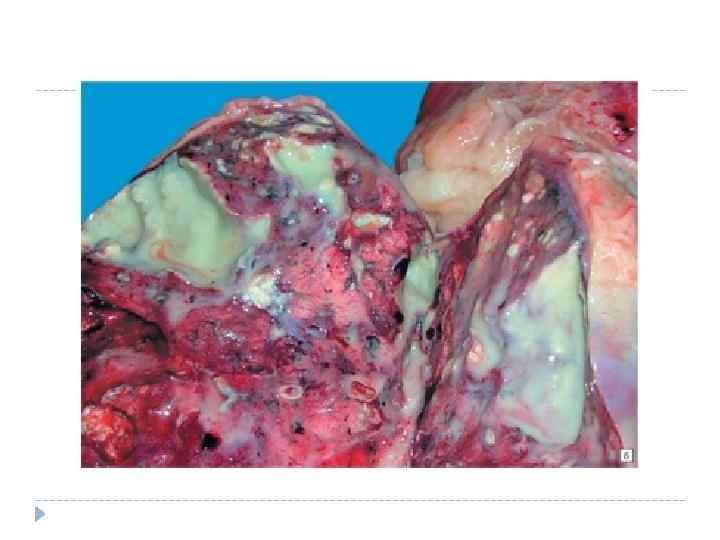

Абсцесс легкого – ограниченное гнойное воспаление легочной ткани с деструкцией ее паренхимы и бронхов, их расплавлением и образованием полости.

Осмотр Осмотр. Определяют отставание пораженной половины грудной клетки в акте дыхания, количество дыхательных движений составляет 20 и более. Кожные покровы могут быть бледными, возможен акроцианоз. Перкуссия. Формируется абсцесс, над ним перкуторный звук притупленный; после вскрытия определяются тимпанит или металлический перкуторный звук (при больших размерах полости). Пальпация. Усиление голосового дрожания (до вскрытия). Аускультация. Ослабленное везикулярное дыхание, усилена бронхофония. После вскрытия определяются звучные влажные хрипы, амфорическое дыхание. Рентгенологическое исследование. До вскрытия абсцесса определяется участок равномерного затемнения с нечеткими округлыми контурами, после вскрытия – полость с четкими границами с горизонтальным уровнем жидкости.

Дополнительное диагностическое исследование Дополнительное диагностическое исследование Проводится общий анализ крови, в котором в период организации определяется нейтрофильный лейкоцитоз с резким сдвигом влево, увеличенная СОЭ, а в период после вскрытия – нормализация показателей; при ХАЛ – нейтрофильный лейкоцитоз со сдвигом влево, увеличение СОЭ. Также проводится иммунологическое исследование крови (лимфопения, повышение активности неспецифического и гуморального звеньев иммунного ответа), иследование мокроты (макро– и микроизучение – цитология, флора, эластичные волокна), рентгенологическое исследование (в период организации – массивное затемнение с нечеткими контурами; после вскрытия в бронх – полость с толстыми, инфильтрированными стенками и с горизонтальным уровнем жидкости; при прорыве в плевру – свободная жидкость и газ в плевральной полости).